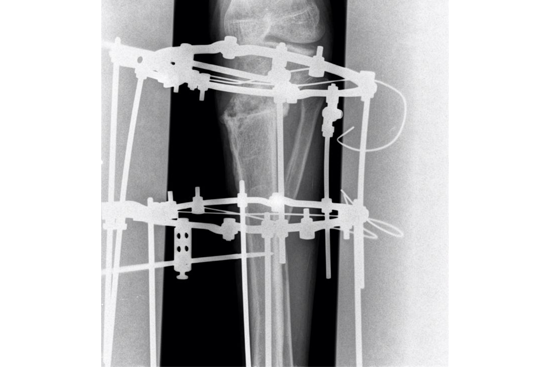

HTO Ilizarov